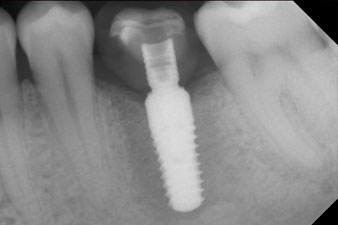

Das Drehmoment beim maschinellen Einbringen war 43 Ncm. Zusätzlich wurde, nach Einschrauben eines speziellen, auf das Implantatsystem abgestimmten Mess-Pfostens (SmartPeg), der ISQ-Wert mit der Sonde des W&H Osstell ISQ Modul bestimmt.

Dieses Modul ist für das Implantmed von W&H optional erhältlich und wird an den Implantologiemotor gedockt (vgl. Abb. 11). Der dimensionslose ISQ-Wert war direkt bei der Insertion 64 in oro-vestibulärer und 68 in mesio-distaler Richtung (Maximalwert = 100). Dies hätte eine offene Einheilung oder sogar Sofortversorgung erlaubt.

Die Abschlussbilder zeigen die verschraubte monolithische Kompositkrone in situ und die Röntgenkontrolle (Abb. 9 und 10) (6).